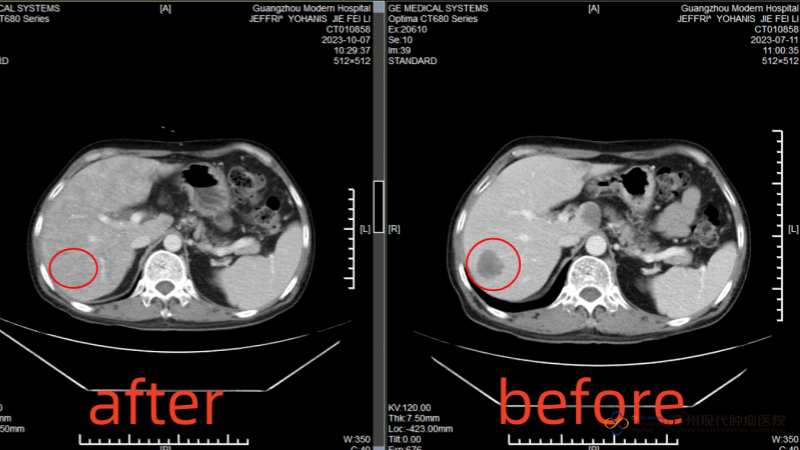

After I arrived at the hospital, the MDT medical team of the hospital consulted me and formulated a comprehensive treatment of "intervention + cryotherapy". Before the treatment, the tumor in the anus was about 29mmx38mm, but after an intervention, the tumor was reduced to 13mmx17mm, and the multiple metastatic foci in the liver were mostly invisible on CT after cryotherapy. Both my wife and I are very happy with this result.

[Comparison of liver tumor size after the first cryotherapy]